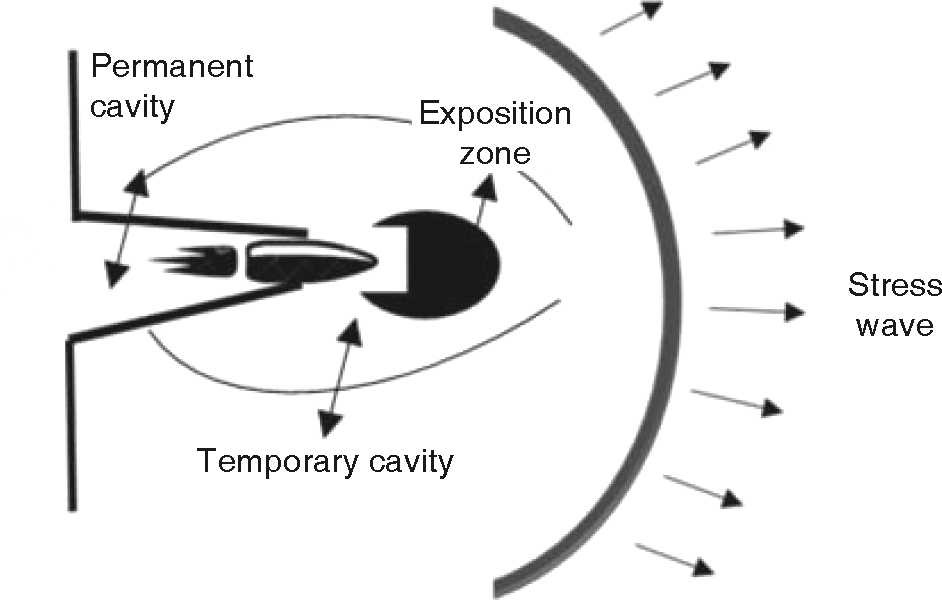

When compared to low speed projectiles, a high speed projectile generates greater kinetic energy, nevertheless, it is wrong to assume they cause greater damage. Injury level depends on many factors: kinetic energy, deformation capability, bullet fragmentation and resistance to deformation exhibited by involved tissue.5,6 In our assessment, not only speed was deemed relevant, impact zone, kinetic energy, bullet characteristics and penetration trajectory were equally deemed relevant in order to define damage as well as to provide prognosis and treatment plan. The moment a projectile enters the body, it creates a permanent cavity measuring a diameter similar to the projectile's; laterally it creates a temporary cavity caused by the expansion of the kinetic energy and forwardly it creates a stress wave (Figure 2).2,4 It must be considered that minimum speed to perforate skin is 50 m/s and to affect bone it is 60 m/s.2 Kinetic energy thus transferred to the body causes changes in tissue circulation, metabolism and electrolytic alterations.7 A critical factor to consider is the inability of bone to absorb energy without fracturing. Glass and bone are similar in their behavior in front of a bullet; energy distribution renders them fragile material.8 Hulke et al, consider several variables of bone damage according to kinetic energy, bullet characteristics and type of tissue: bone depression, simple fracture, comminuted fractures or full separation of bone segments. A high speed projectile can produce bone fragments which in turn will exit as projectiles in the direction of the bullet's entrance. When contacting the bone, the projectile might become deformed or fragment, causing thus greater damage to the soft tissue.3